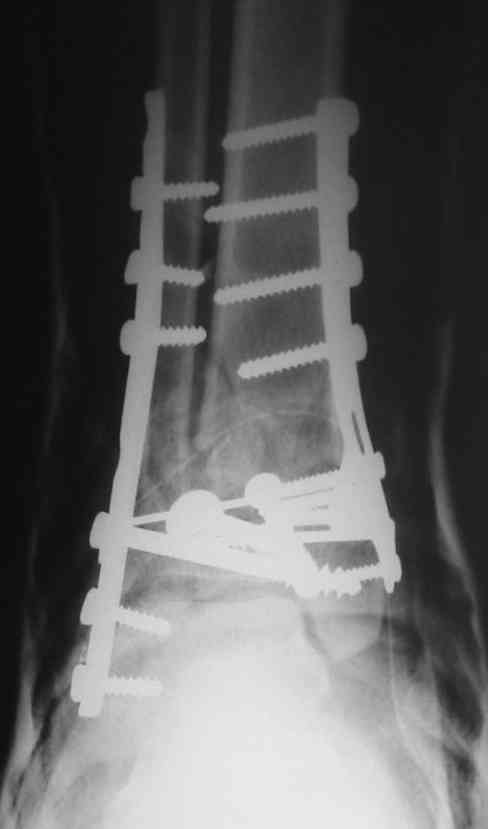

OK, Dr Driagin,

Ja operiroval bolnogo po Vashemu, hotia sam ni ochen' ubezden' v itom, t.k. bolnoi otkazalsa na proch' ot ex.fix, ja emu sdelal ORIF + Kostnia plastika, snimky prelogiottsa,

Isskrenny Vash Castro